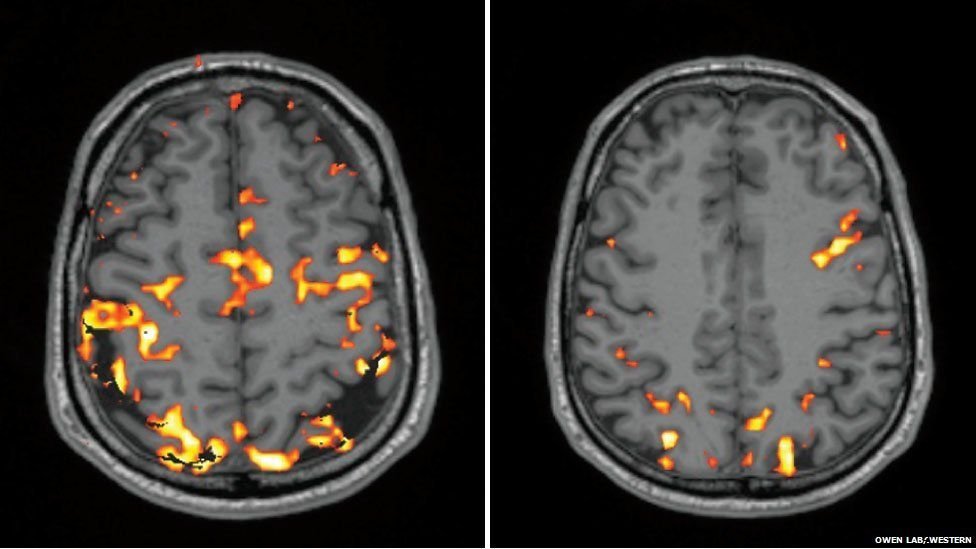

Look at this image.

On the left is a normal night of sleep. On the right is when it's deprived of 4 hours of sleep.

The colored areas show brain activity. Notice the lack of activity on the right side.

Sleep deprivation affects decision-making & problem-solving.